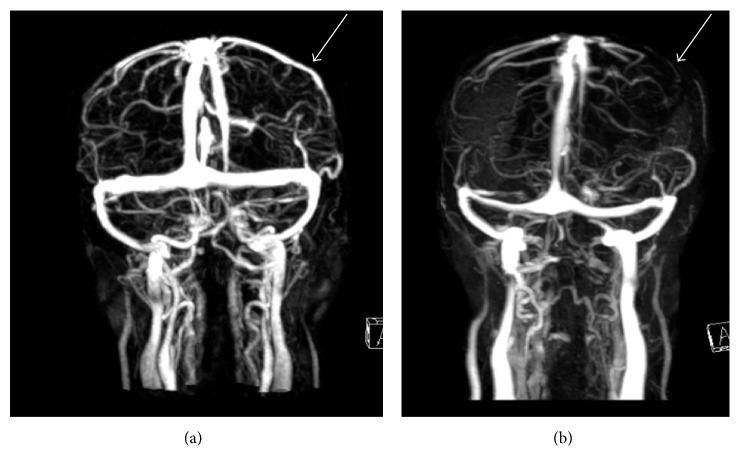

Figure 3.

Contrast-enhanced MRV of the brain is performed on day 10 (a) and day 16 (b). There is patent left vein of Trolard on day 10 with good collateral flow involving the left frontoparietal region. However, on day 16, there is thrombosis of the left vein of Trolard with slight decrease in collateralization within the left frontoparietal region, compatible with venous thrombosis and hemorrhagic venous infarct.